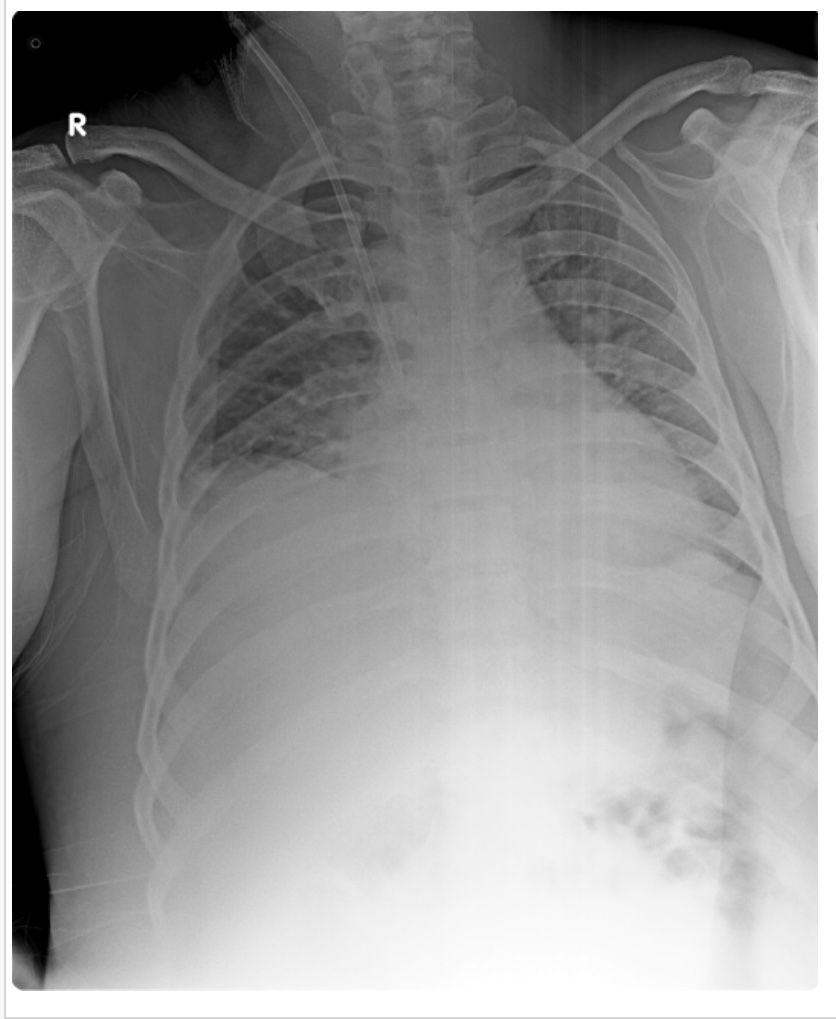

X Ray chest:

Rt sided pleural effusion with consolidation.

Post pleural tap chest X Ray